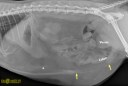

Une souris bionique, voilà ce qu’il avait mangé !